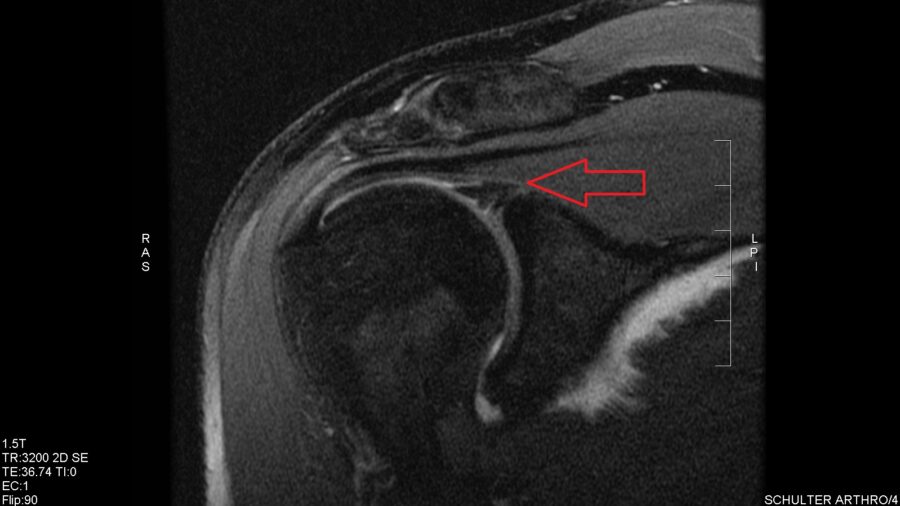

Epaule Arthro IRM : anatomie normale | e-Anatomy

Doit On Se Deshabiller Pour Une Irm De Lépaule IRM de l'épaule : anatomie normale | e-Anatomy

Doit On Se Deshabiller Pour Une Irm De Lépaule Epaule Arthro IRM : anatomie normale | e-Anatomy